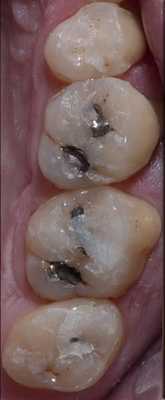

Пациент обратился за помощью с несколькими основными жалобами, главной из которых являлась эстетическая дилемма: ему не нравился цвет, размер и форма зубов (фото 1). При этом он также желал по возможности закрыть диастему между 10 и 11 зубами. Он также был обеспокоен «объемом» собственной улыбки и хотел расширить форму зубной дуги так, чтобы улыбка казалась более полной. Во время стоматологического осмотра было установлено, что пациент имел умеренную степень стирания режущих и окклюзионных поверхностей, легкую генерализированную форму рецессии с локализированной умеренной рецессией в области первых моляров верхней челюсти. Большинство боковых зубов имели амальгамные реставрации небольших и средних размеров с признаками вторичного кариеса. На 18 и 29 присутствовали металлокерамические конструкции. Все передние зубы верхней челюсти и несколько передних зубов нижней челюсти имели композитные пломбы в интерпроксимальных зонах, которые со временем изменили свой цвет.

Фото 15-21. Последовательность клинических процедур: вид до вмешательства, вид прототипа, удаление прототипа, дефектных амальгамных пломб и остальных реставраций, нанесение кариес-маркера, запечатывание дентина и заполнение поднутрений, установка окончательных реставраций.